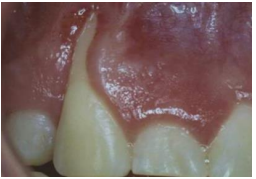

Analise a imagem abaixo, que apresenta um achado, para responder à questão 37.

(Carranza 2016).

Com base na imagem acima, verifica-se